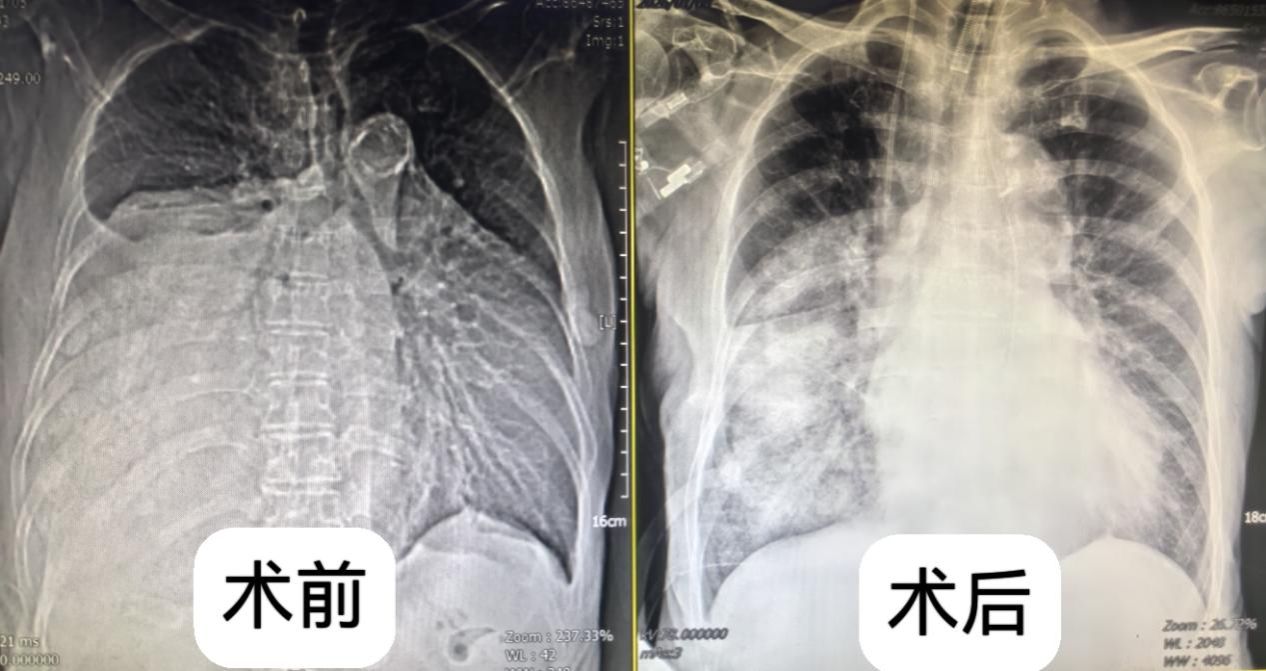

一年前,叶奶奶在体检中偶然发现纵隔占位性病变,当时肿瘤直径约 4 厘米,因无明显不适症状,且考虑到年龄较大,家属选择了保守观察。然而近半年来,患者逐渐出现活动后气喘、心慌等症状,近期更是发展到体力无法支撑正常行走,体重也随之下降。复查胸部 CT 显示,肿瘤已增至超过15厘米,占据右侧胸腔超过2/3空间,严重压迫心脏、大血管及食管,且与周围组织粘连致密,若不及时干预,随时可能因呼吸循环衰竭危及生命。

手术当日,在麻醉科团队的精准调控下,手术正式开始。由于肿瘤与周围肺组织、食管粘连紧密,团队采用 “精细剥离 +膜内完整切除” 的方式,小心翼翼地避开关键结构,逐一处理肿瘤滋养血管。经过1小时的精细操作,重达3500 克以上,直径超过20cm的巨大肿瘤被完整切除,术中出血量控制在 100 毫升以内,未损伤任何重要神经血管及组织,完美解除了肿瘤对肺脏及心脏的压迫。